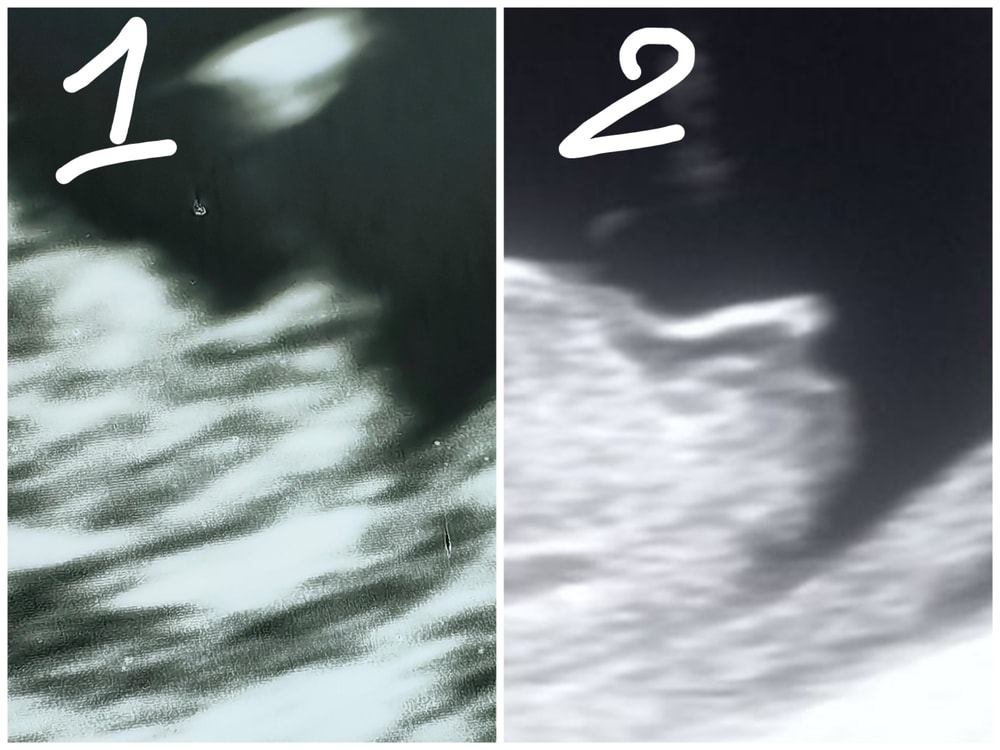

1. Мой снимок

2. Подтвержденная девочка из интернета